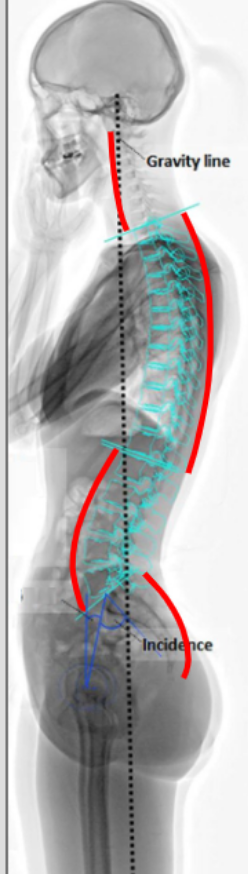

What is the morphology of the vertebral column?

• embryos = spine is C shaped

• when we learn how to walk our muscle start to build and form the primary curvature => thoracic kyphosis and sacro-coccygeal kyphosis

• as we get older and excersise, body weight shifts and secondary curvatures form => lumbar lordosis and cervical lordosis

what are the primary and secondary curvatures that form as we get older?